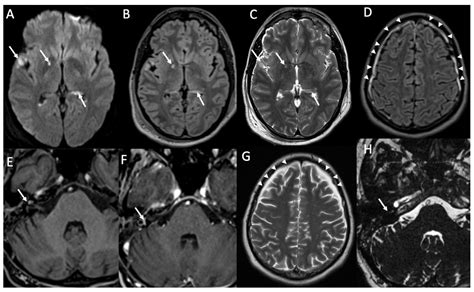

Diagnosing encephalitis involves a combination of clinical evaluation, laboratory tests, and imaging studies. The diagnostic process typically includes:

• Imaging Studies: Magnetic resonance imaging (MRI) and computed tomography (CT) scans to visualize brain inflammation and rule out other conditions.

Diagnosing meningitis involves a combination of clinical evaluation, laboratory tests, and imaging studies. The diagnostic process typically includes:

• Imaging Studies: Magnetic resonance imaging (MRI) and computed tomography (CT) scans to visualize inflammation and rule out other conditions.